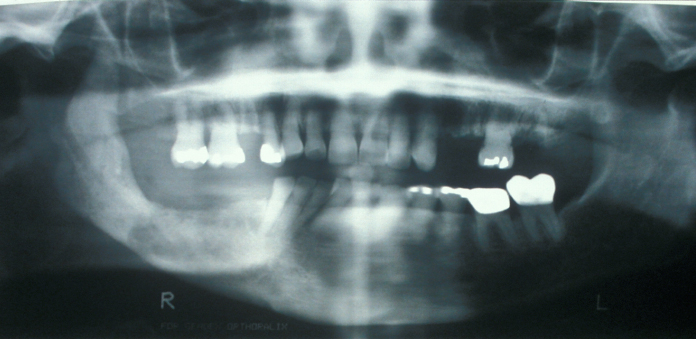

Imaging may be difficult because the radiographic findings lag behind the clinical stage. The first radiographic sign (see Figure 3) may be radiopacity which represents the sequestrum that has lost its non-mineralised components. Bone scans (PET scans) show osteomyelitis as areas of increased bone turnover (‘hot spots’).

Figure 3: Chronic osteomyelitis of the right mandible. Note the loss of the right condyle (part of the mandible forming the jaw joint) and the diffuse radiopacity of the right body of the mandible.